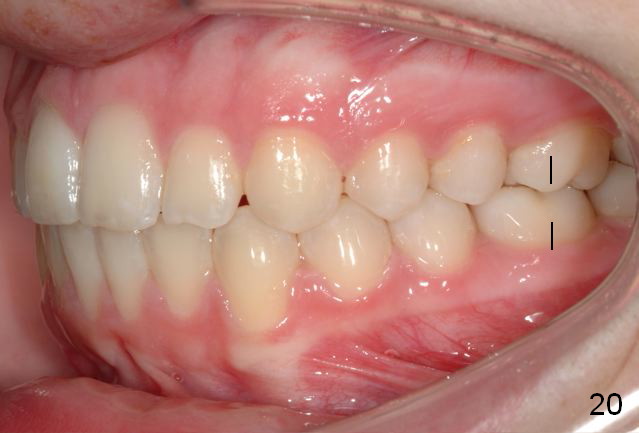

Final Results of Unilateral Class II Malocclusion

After using Rapid Molar Distalizer.  Total treatment lasts 50 months.